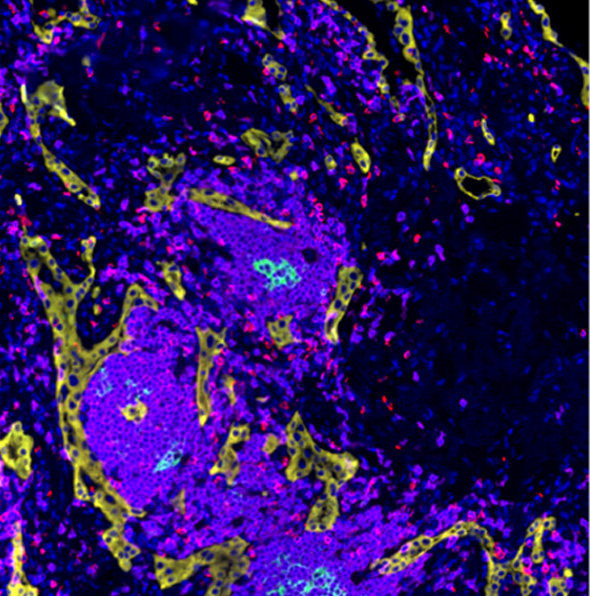

Nucleus,CD4,CD8,CD21,CD31,Ki-67,FoxP3,Pan-CK

空间浸润分析用于分析病灶区域(如肿瘤、坏死、纤维化等)周围某类细胞的浸润情况。如常用于肿瘤免疫浸润分析。

通过识别组织图像中标志物的染色信息,自动调节荧光强度并识别出图像中 TLS 结构进行标注,进一步定量分析可得到图像中每个 TLS 独立的定量数据,同时可进一步对三级淋巴结构的内部进行空间分析。